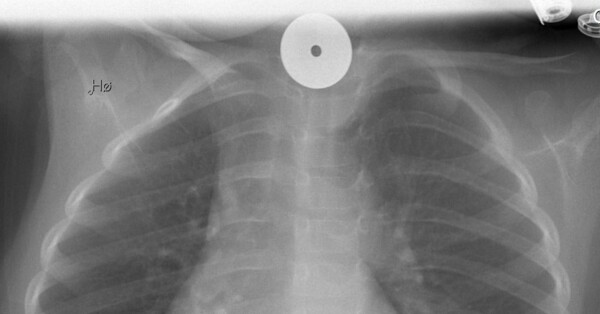

Her Svelger Ingrid Maria 3 En Krone Helse